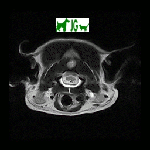

RESONANCIA MAGNÉTICA

AXIAL